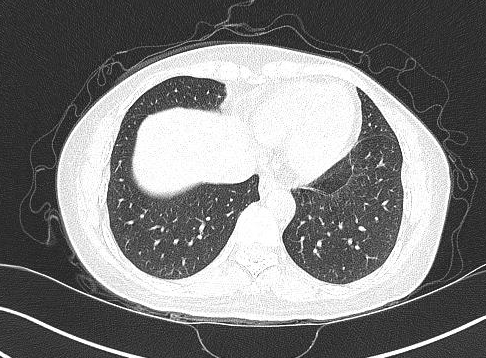

双上肺可见纤维条索状影

窦性心律,胸部ct提示双肺散在多发微小结节灶,右肺中叶少许纤维条索灶

肺ct报告有这些词你就放心吧1,纤维条索影多为肺内炎症后遗留下来的

肺部纤维条索灶在ct上什么表现代表了什么意义医生讲解